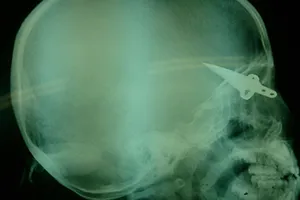

Chùm ảnh bé bị dao đâm vào đầu bụ bẫm trong ngày tái khám

Vụ bé sơ sinh bị đâm dao vào đầu: Bé vẫn còn hôn mê

Kẻ lạ mặt đâm dao vào đầu bé trai 11 ngày tuổi ngay tại bệnh viện

Hội chẩn từ xa cứu cháu bé bị dao găm vào não